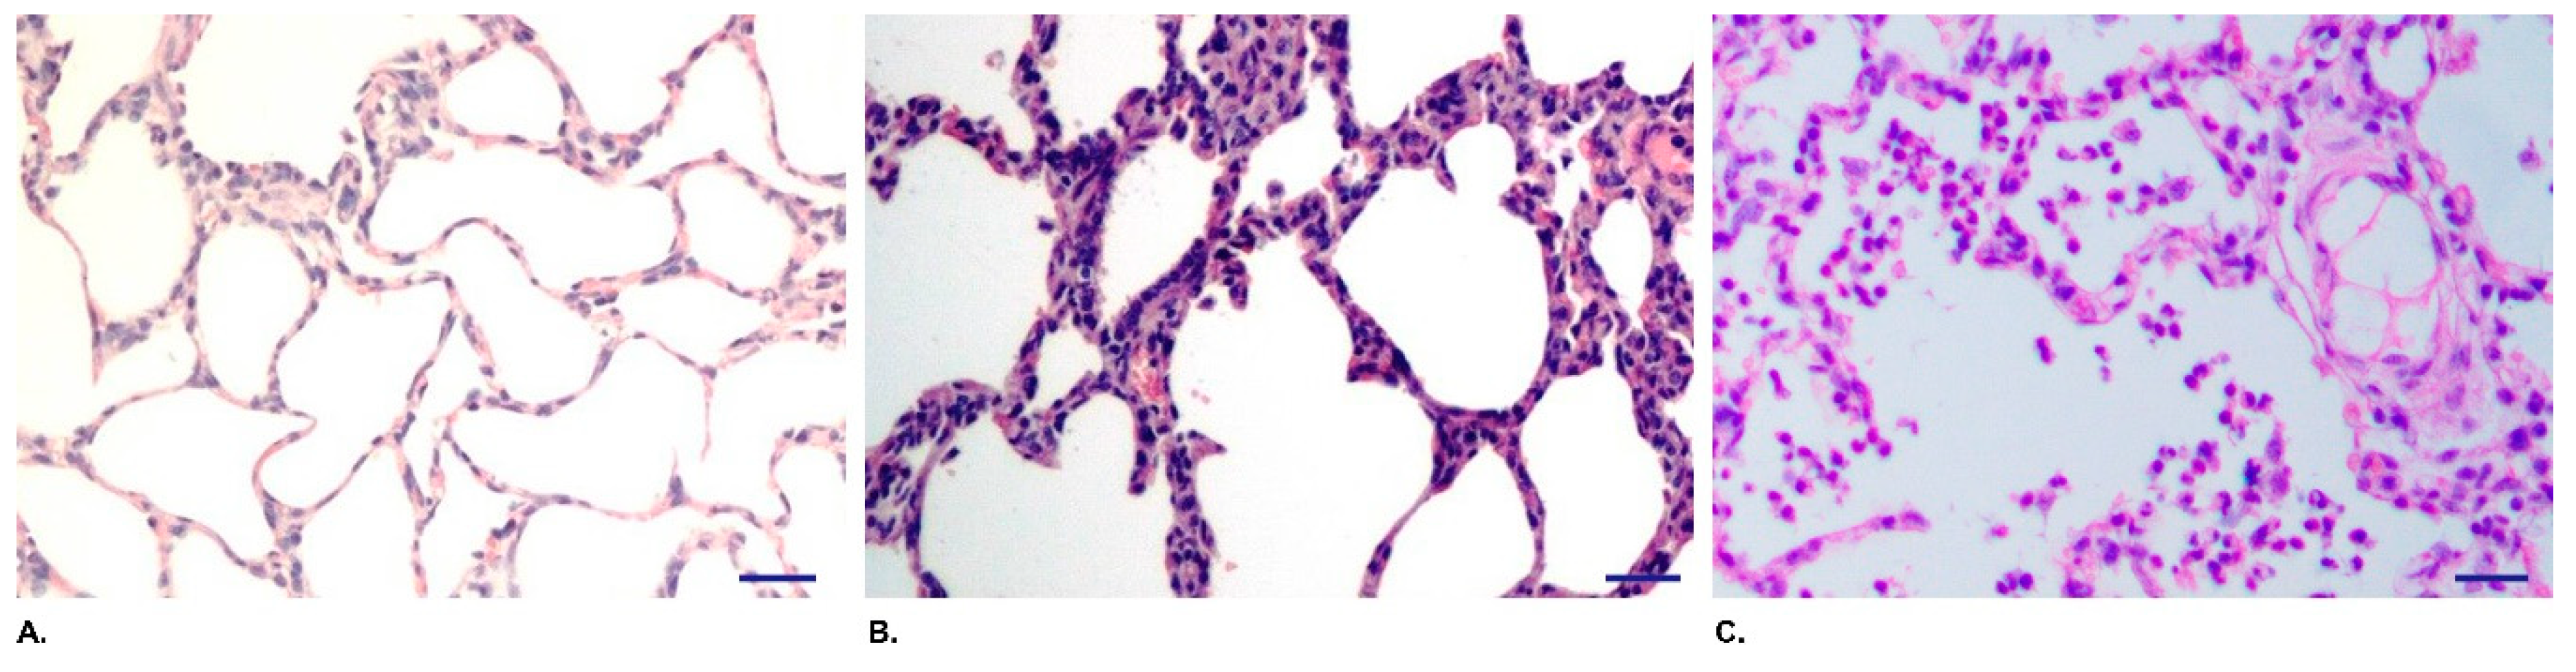

3.3. QH09 Was Safe to Piglets

3.4. QH09 Induced High Levels of Antibodies and Conferred Protection Against Lethal Challenge